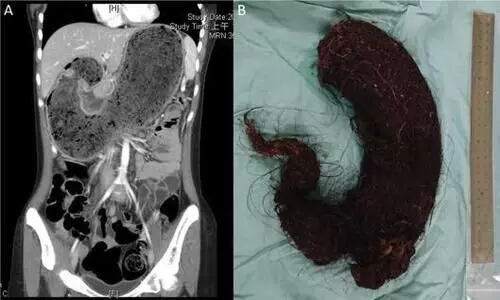

ലഖ്നോ: ഉത്തർപ്രദേശിൽ പ്രായപൂർത്തിയാകാത്ത പെൺകുട്ടിയുടെ വയറ്റിൽനിന്ന് ഡോക്ടർമാർ ശസ്ത്രക്രിയയിലൂടെ പുറത്തെടുത്തത്...

കുട്ടിയുടെ വയറിനുള്ളിൽ മുടിയുടെ വലിയ ശേഖരം കണ്ടെത്തി